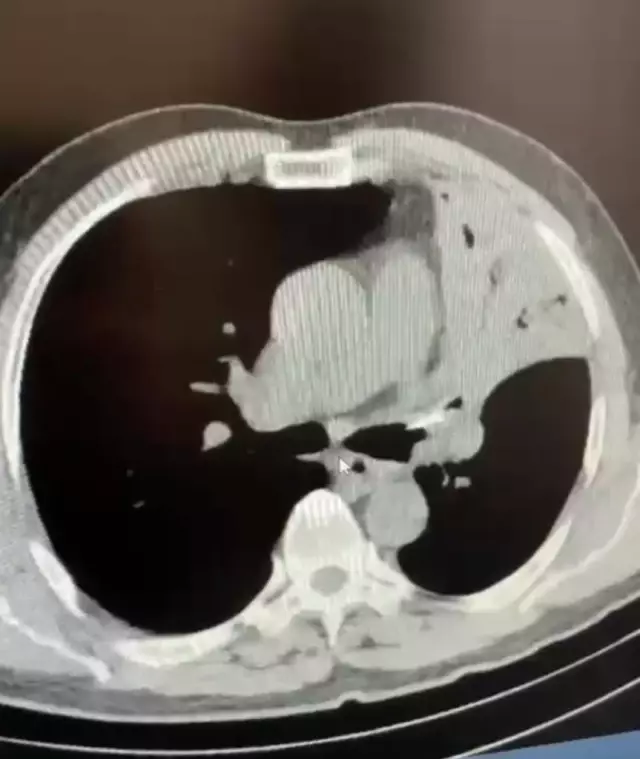

Uzun süredir öksürük, şiddetli ağrı ve sırtında yanma şikayetleri bulunan bir kişi, Bolu'da gittiği hastanede 5 yıl önce sol akciğerine saplanan lades kemiğiyle yaşadığını öğrendi. Ameliyata alınan şahıs, kemiğin çıkarılması sonucu sağlığına kavuştu.

Fer'in yapılan muayenesinde sol akciğerine lades kemiği saplandığı tespit edildi. Fer'in 5 yıl boyunca akciğerinde saplanmış halde bulunan lades kemiği yapılan ameliyatla alındı. Sağlığına kavuşan Fer, yapılan son kontrollerinin ardından taburcu edildi.

5 yıl boyunca öksürük, şiddetli ağrı ve sırtında yanma şikayetleri bulunduğunu ifade eden Mehmet Salih Fer, "Aynı şikayetlerle hastanelere gittim, muayenelerim yapıldı, filmler çekildi. Sık sık enfeksiyon geçiriyordum, farklı farklı tanılar konuldu ve ilaç tedavileri başlatıldı. Ancak hiçbir sonuç alamadım ve şikayetlerim devam etti. Son olarak İzzet Baysal Eğitim ve Araştırma Hastanesi Göğüs Cerrahisi kliniğine geldim. Burada doktorlarım tarafından muayenelerim ve tetkik işlemlerim yapıldı. Neticede sol akciğerimde yaklaşık 5 senedir bir lades kemiği ile yaşadığımı öğrendim" dedi.